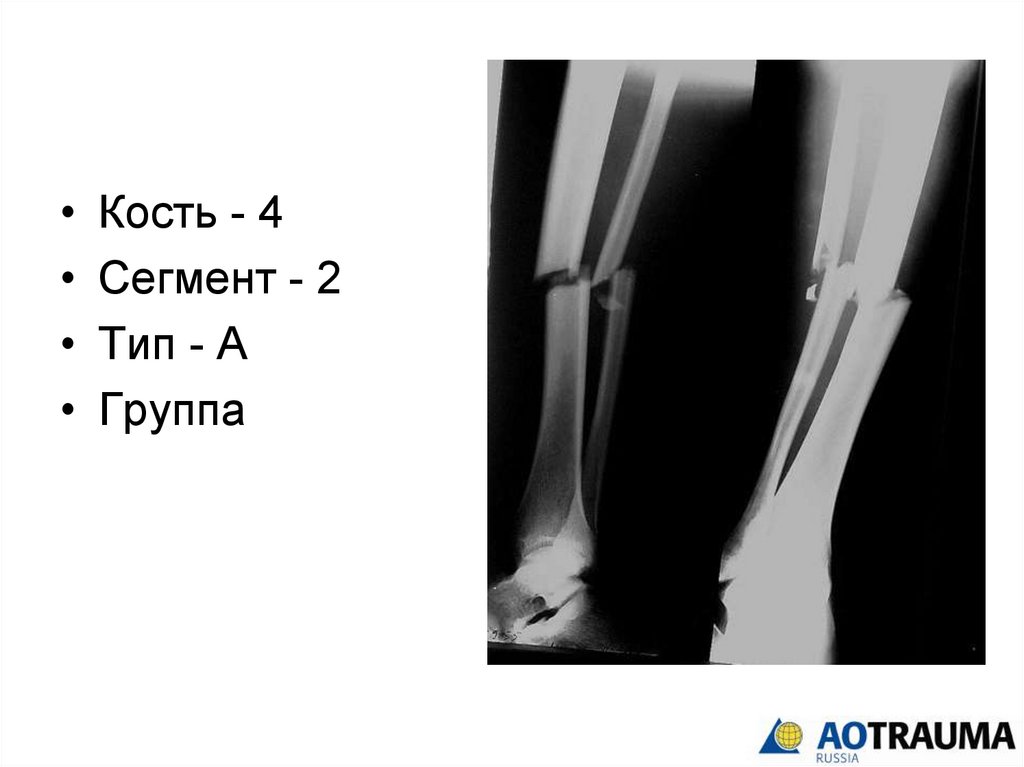

Кость - 4

Сегмент

Тип

группа

Сегмент - 2

33.

Тип - А